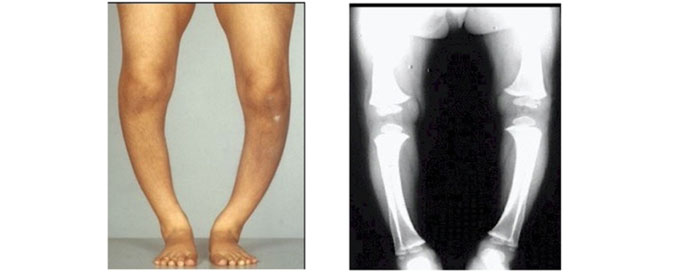

Rickets, most commonly due to nutritional deficiency of Vitamin D3 and dietary calcium leads to softening of bones and Curving of bones during growth.

• Deformities in bone structure (e.g., bowed legs in rickets)